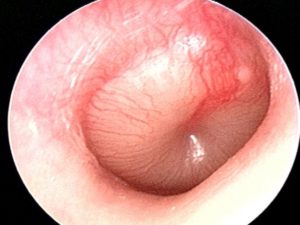

- Микроскопия. Это обследование назначют для того, чтобы дифференцировать дефекты барабанной перепонки и заболевание наружного уха.

В ходе диагностических исследований отоларингологу необходимо исключить наличие других заболеваний, сопровождающихся понижением слуха (болезни Меньера, отита, отосклероза, инородного тела уха, лабиринтита).

Электрокохлеография дает возможность дифференцировать кохлеарный неврит от болезни Меньера. Для исключения заболеваний наружного уха и изменений со стороны барабанной перепонки проводится отоскопия и микроотоскопия.